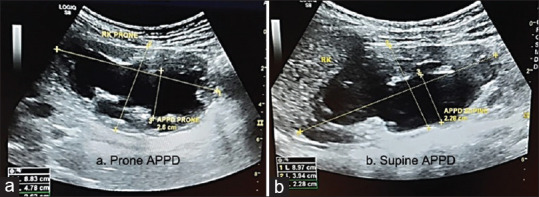

Background: Ureteropelvic junction obstruction (UPJO) is the most common cause of antenatal hydronephrosis. Although majority of them improve with time, none of the existing diagnostic modalities can accurately predict which hydronephrotic kidney is at the risk of progressive renal damage and will benefit from early surgery. Postural variations in the anteroposterior pelvic diameter (APPD) of the hydronephrotic kidney in children during follow-up postnatal ultrasonography (USG) reflect the intrapelvic tension, which might help in predicting the need of surgery amongst these patients.

Results: We found a higher prone APPD than supine APPD in all these patients indicating the obstruction at ureteropelvic junction. However, in the surgical group, there was less variation in the postural APPD compared to the conservative group, and when there was no variation in the postural APPD, the need of surgery was 100%. The limitation of our study was the small sample size (n = 36). A study involving a larger population or involving multiple institutions may further add significance to our findings.

Conclusion: We found less postural variation in APPD on USG to be more likely associated with severe UPJO requiring early surgery. This may indicate a non-compliant renal pelvis. However, it was statistically not significant.